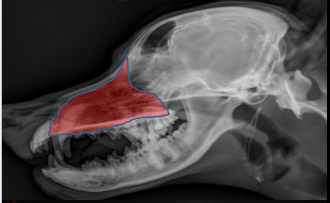

ID

Maxilla

Zygomatic Bone

Orbital Margin

Coronoid Process of Mandible

ID Radiographic View

Open Mouth VD view of Nasal Cavity